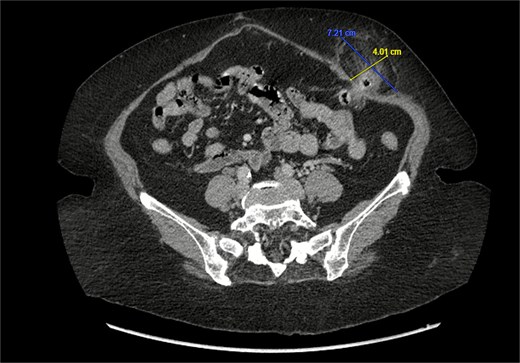

A 76-year-old female with a medical history of type 2 diabetes mellitus (controlled with oral medications), hypertension (on two medications), hyperlipidemia (on atorvastatin), and recently diagnosed Alzheimer’s disease (started on memantine) presented to the emergency department with severe left-sided abdominal pain of 2 days’ duration. The pain began gradually but worsened significantly in the last few hours. It was associated with a bulging mass in the abdomen that was tender and painful to touch. The patient reported that the swelling had been present for 2 years, intermittently reducible with minimal exertion. However, since the previous day, it had become irreducible and increasingly painful, particularly after a failed attempt to reduce it manually at home. She also admitted to chronic constipation for years, usually treated with oral laxatives, though she had not been compliant with them recently. Her surgical history included a laparoscopic cholecystectomy combined with paraumbilical hernia repair using mesh 3 years ago. Upon examination by the on-call surgical team, the patient was afebrile with stable vital signs. Her abdomen was distended, and a 7 × 7 cm irreducible, tender mass was noted over the left side. An urgent computed tomography (CT) scan of the abdomen and pelvis with intravenous and oral contrast revealed a left lateral ventral abdominal hernia traversing the left lateral oblique muscles. The hernia sac contained omental fat and an inflamed diverticulum of the transverse colon, with surrounding inflammatory changes. The defect measured 1.4 × 1 cm, and the hernia sac measured 6.7 × 4.2 × 4 cm. No free fluid, fluid collections, or pneumoperitoneum were identified (Figs 1–3).

Coronal section of CT abdomen and pelvis showing the ventral hernia.

Sagittal section of CT abdomen and pelvis showing the ventral hernia.